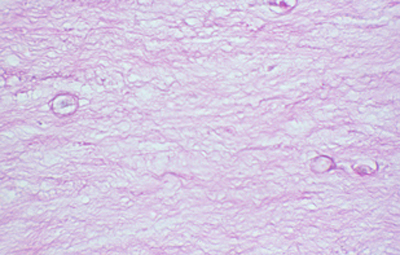

Cuando el examen patológico se realiza en cortes de tejido corneal procesados en parafina, (biopsias y discos de córnea de queratoplastias) las coloraciones que empleamos usualmente son la coloración de Hematoxilina-Eosina (Figura 49), el Blanco de Calcofluor. (Figura 50), la de PAS (Figura 51 y 52). De nuevo, la consideración de que una infección corneal puede ser causada por Acantamoebas es la condición indispensable en el diagnóstico diferencial para llegar a su diagnóstico

Fig. 51 PAS, Original x160

Fig. 52 PAS, Original x160